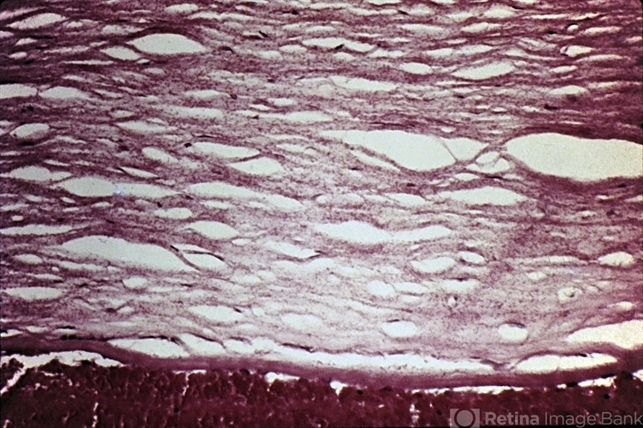

- blood-staining, cornea, stroma

- Blood-staining of the cornea. Note the myriad of minute red granules throughout the corneal stroma.